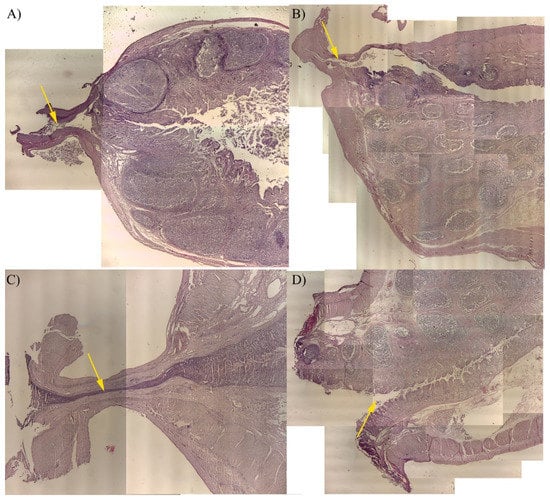

2.7. Histology

3.3. Histology